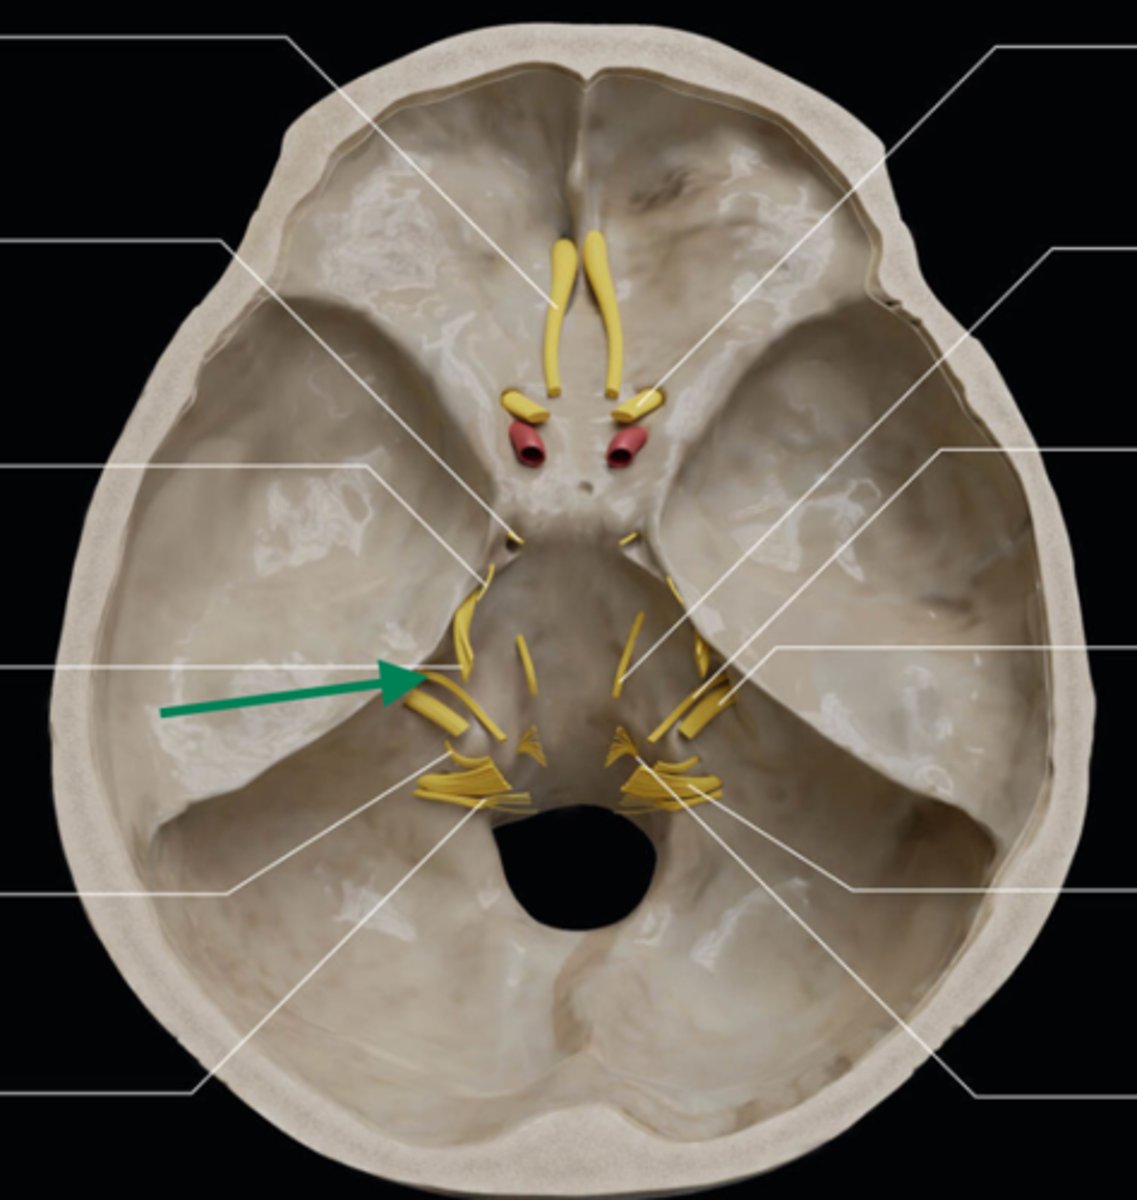

olfactory bulb

olfactory tract

optic nerve (CN II)

internal carotid artery

oculomotor nerve (CN III)

trochlear nerve (CN IV)

abducent nerve (CN VI)

trigeminal nerve (CN V)

facial nerve (CN VII)

vestibulocochlear nerve (CN VIII)

glossopharyngeal nerve (CN IX)

vagus nerve (CN X)

accessory nerve (CN XI)

hypoglossal nerve (CN XII)